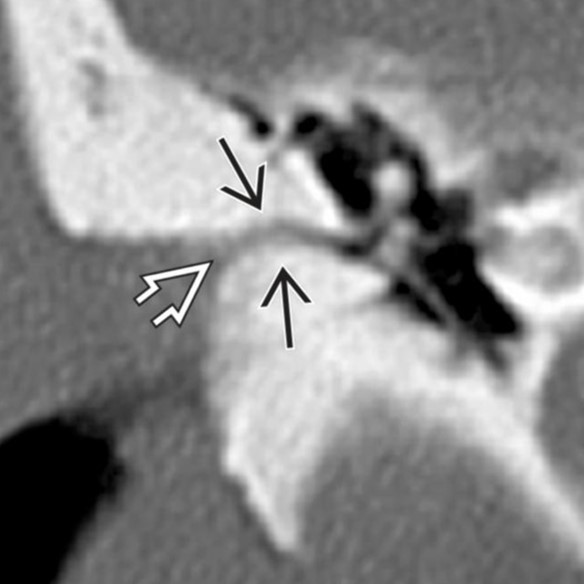

Medial epitympanic congenital cholesteatoma that erodes portions of the ossicles.

Solid arrow: choleastatoma

open arrow: erosion of the long process of the incus and hub of the stapes

Curved arrow: erosion of the lateral bony margin of the tympanic segment of the facial nerve canal